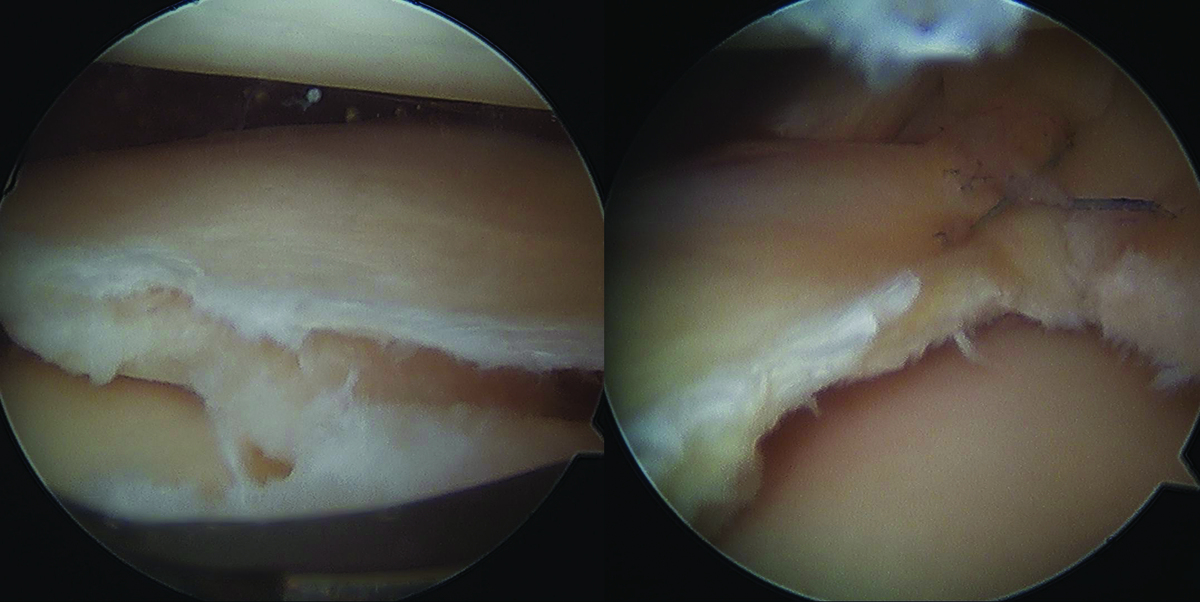

반월상 연골판 파열 후 무릎통증… ‘이럴 때’ 주사치료 도움

대표적인 수술법으로 연골판 봉합술, 부분 절제술, 그리고 연골판 이식술을 들 수 있다. 연골판 봉합술은 찢어진 연골을 실로 꿰매어 원래의 위치로 복원하는 방법이다. 혈액 공급이 비교적 풍부한 외측 부위의 파열일수록 회복 가능성이 높으며, 젊고 활동적인 환자에게 적합하다. 연골판 절제술은 손상된 부위만 부분적으로 제거해 통증을 줄이는 방법으로, 회복이 빠르다는 장점이 있지만 연골의 일부가 없어지기 때문에 장기적으로 관절염 위험이 증가할 수 있다.